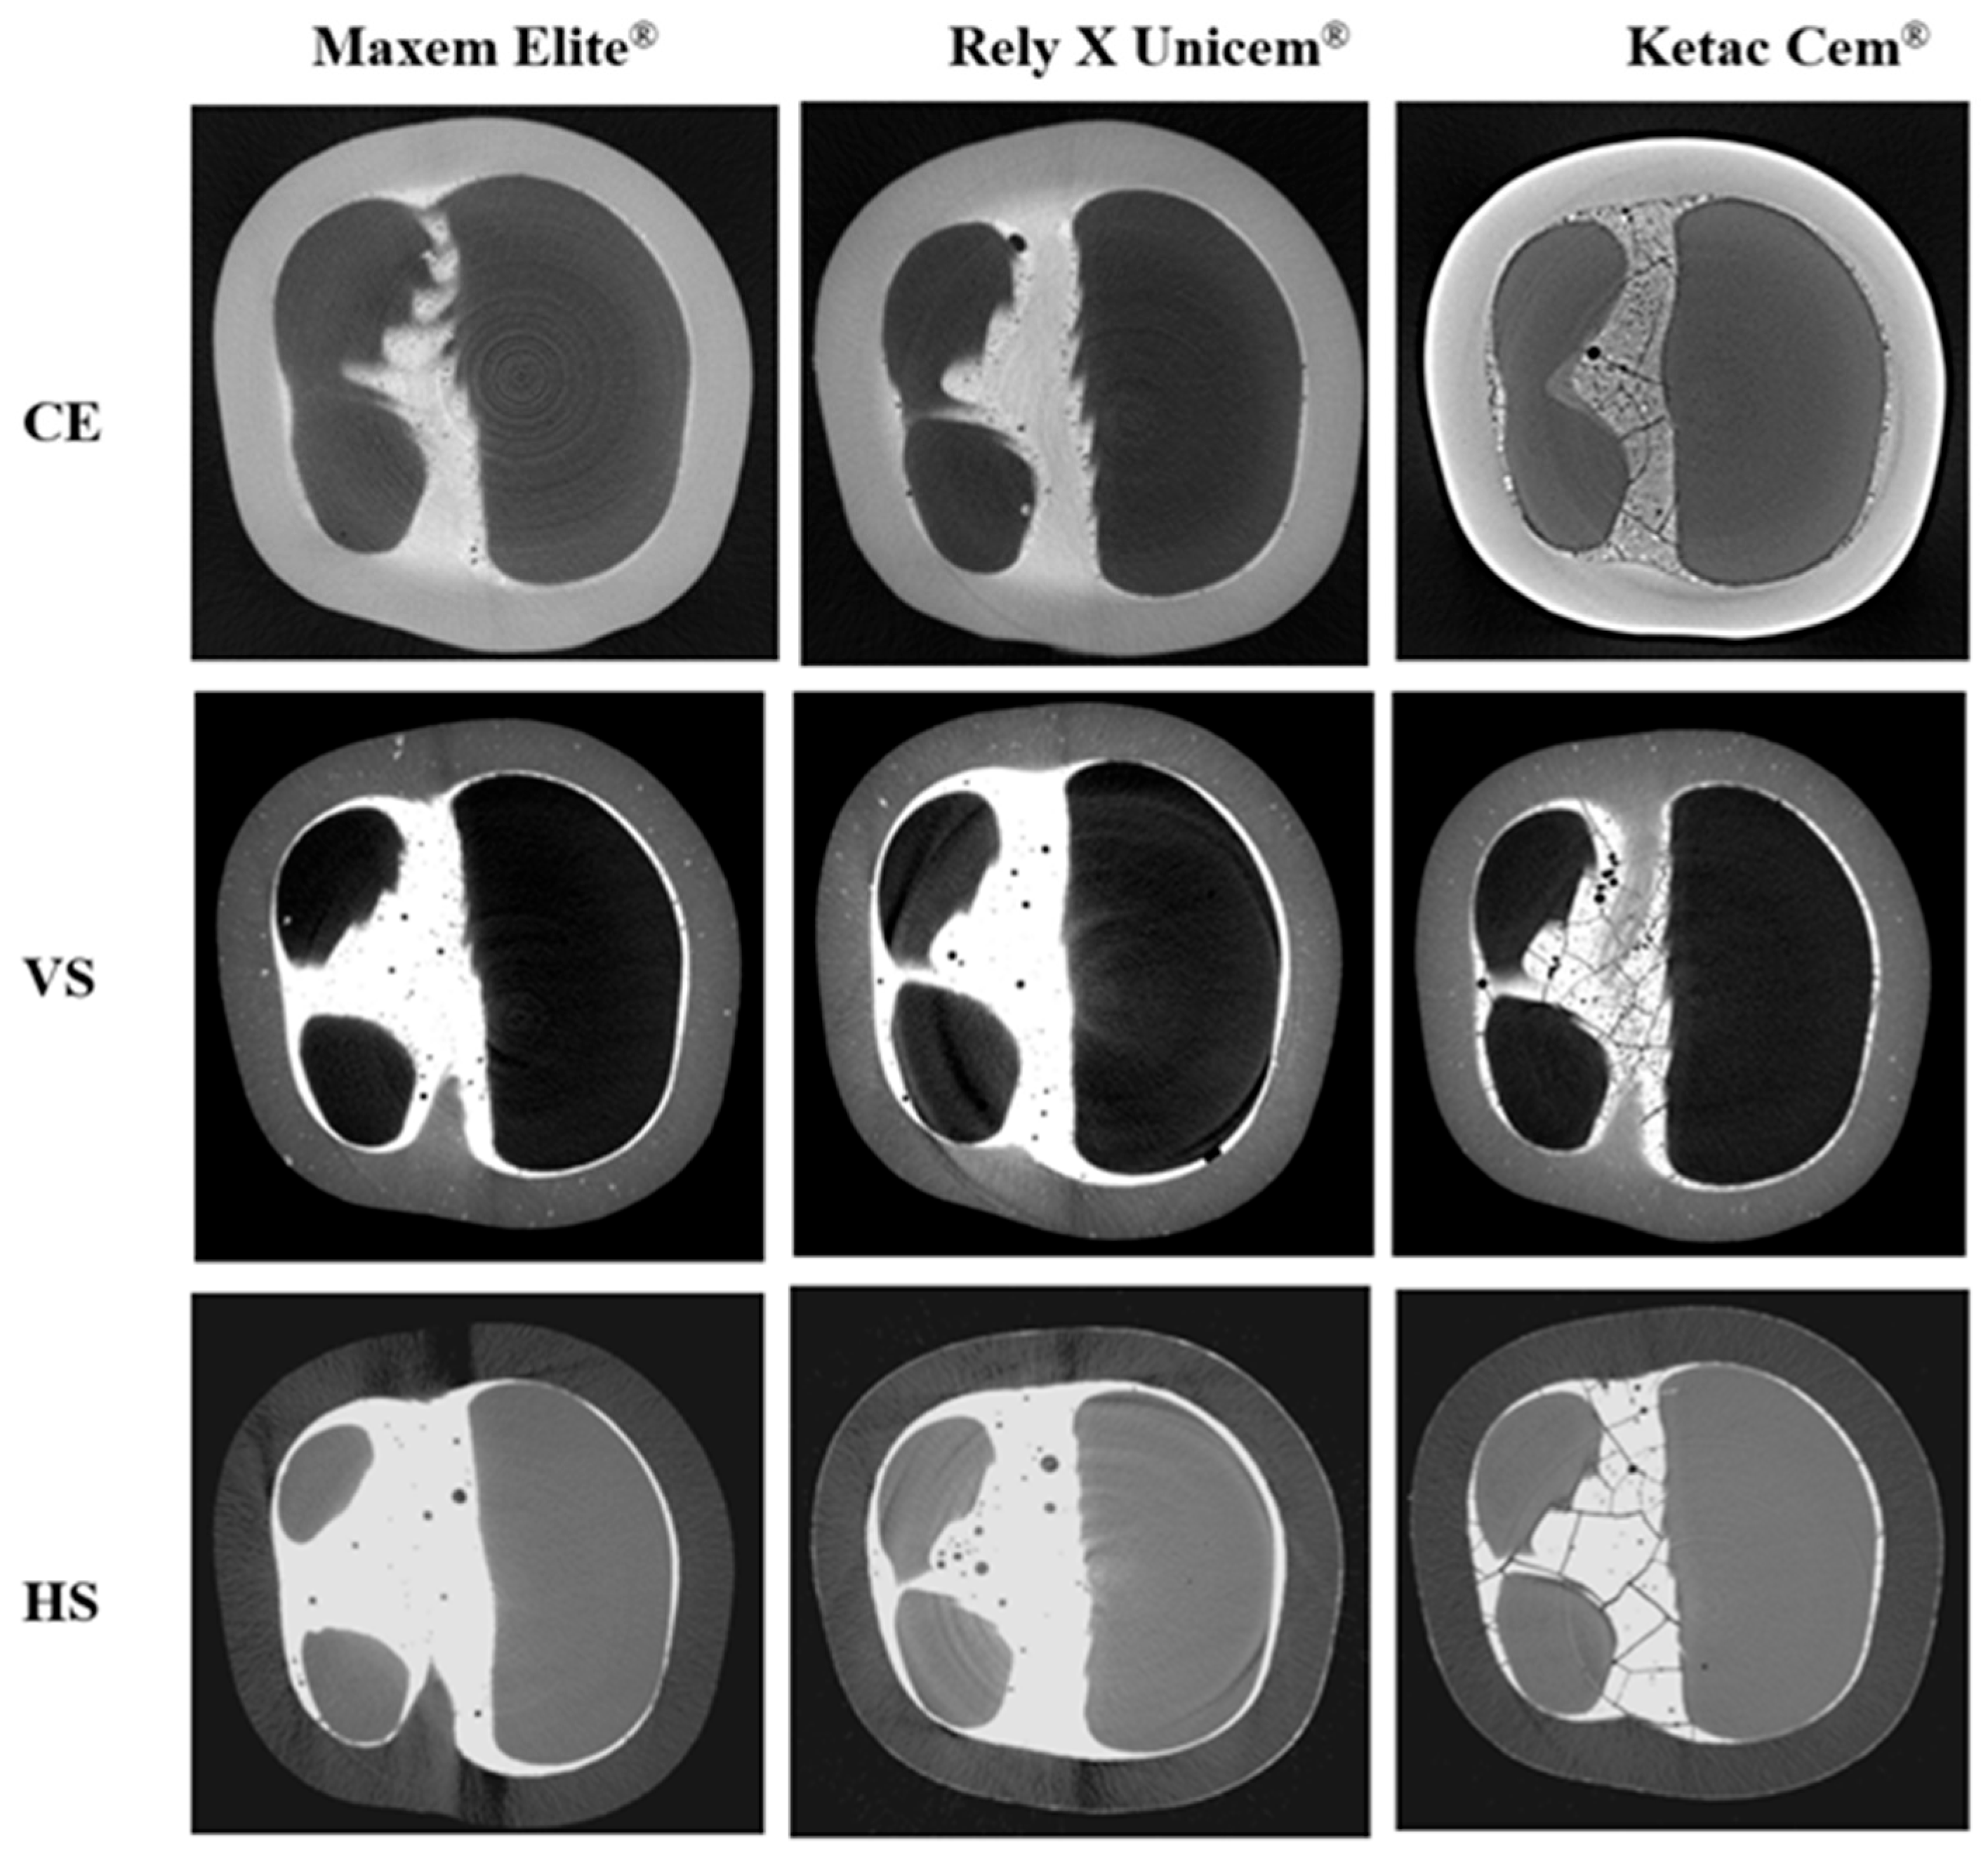

3.2. Micro-CT Analysis

| Types of Ceramic | Luting Cement | Cracked Crowns (n) | Fractured Crowns (n) | Mean ± SD (N) | Min. (N) | Max. (N) |

|---|---|---|---|---|---|---|

| Cerasmart® 270 (CE) | Maxem Elite® (n = 11) | 0 | 0 | >2000 | N/A | N/A |

| Rely X Unicem® (n = 11) | 0 | 0 | >2000 | N/A | N/A | |

| Ketac Cem® (n = 11) | 0 | 4 | 2000 | 2000 | 2000 | |

| VarseoSmile Crown Plus® (VS) | Maxem Elite (n = 11) | 0 | 0 | >2000 | N/A | N/A |

| RelyX Unicem® (n = 11) | 0 | 0 | >2000 | N/A | N/A | |

| Ketac Cem® (n = 11) | 4 | 7 | 1795.2 ± 156.7 | 1689.9 | 1980.0 | |

| Hassawat-01 (HS) | Maxem Elite® (n = 11) | 0 | 0 | >2000 | N/A | N/A |

| Ketac Cem® (n = 11) | 11 | 0 | 1732.6 ± 127.3 | 1540.6 | 1875.6 |